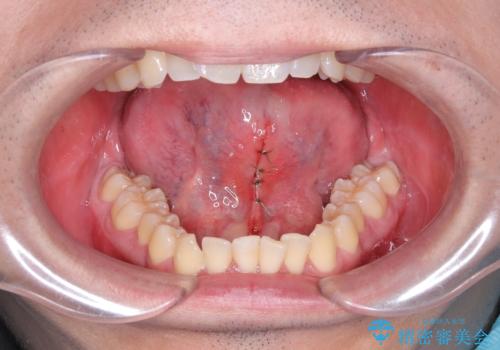

手術は局所麻酔下で行われ、舌小帯を切開し、縫合します。

手術後は、通常、数日から数週間で回復します。痛みや腫れがある場合は、医師の指示に従って適切な処置を行います。